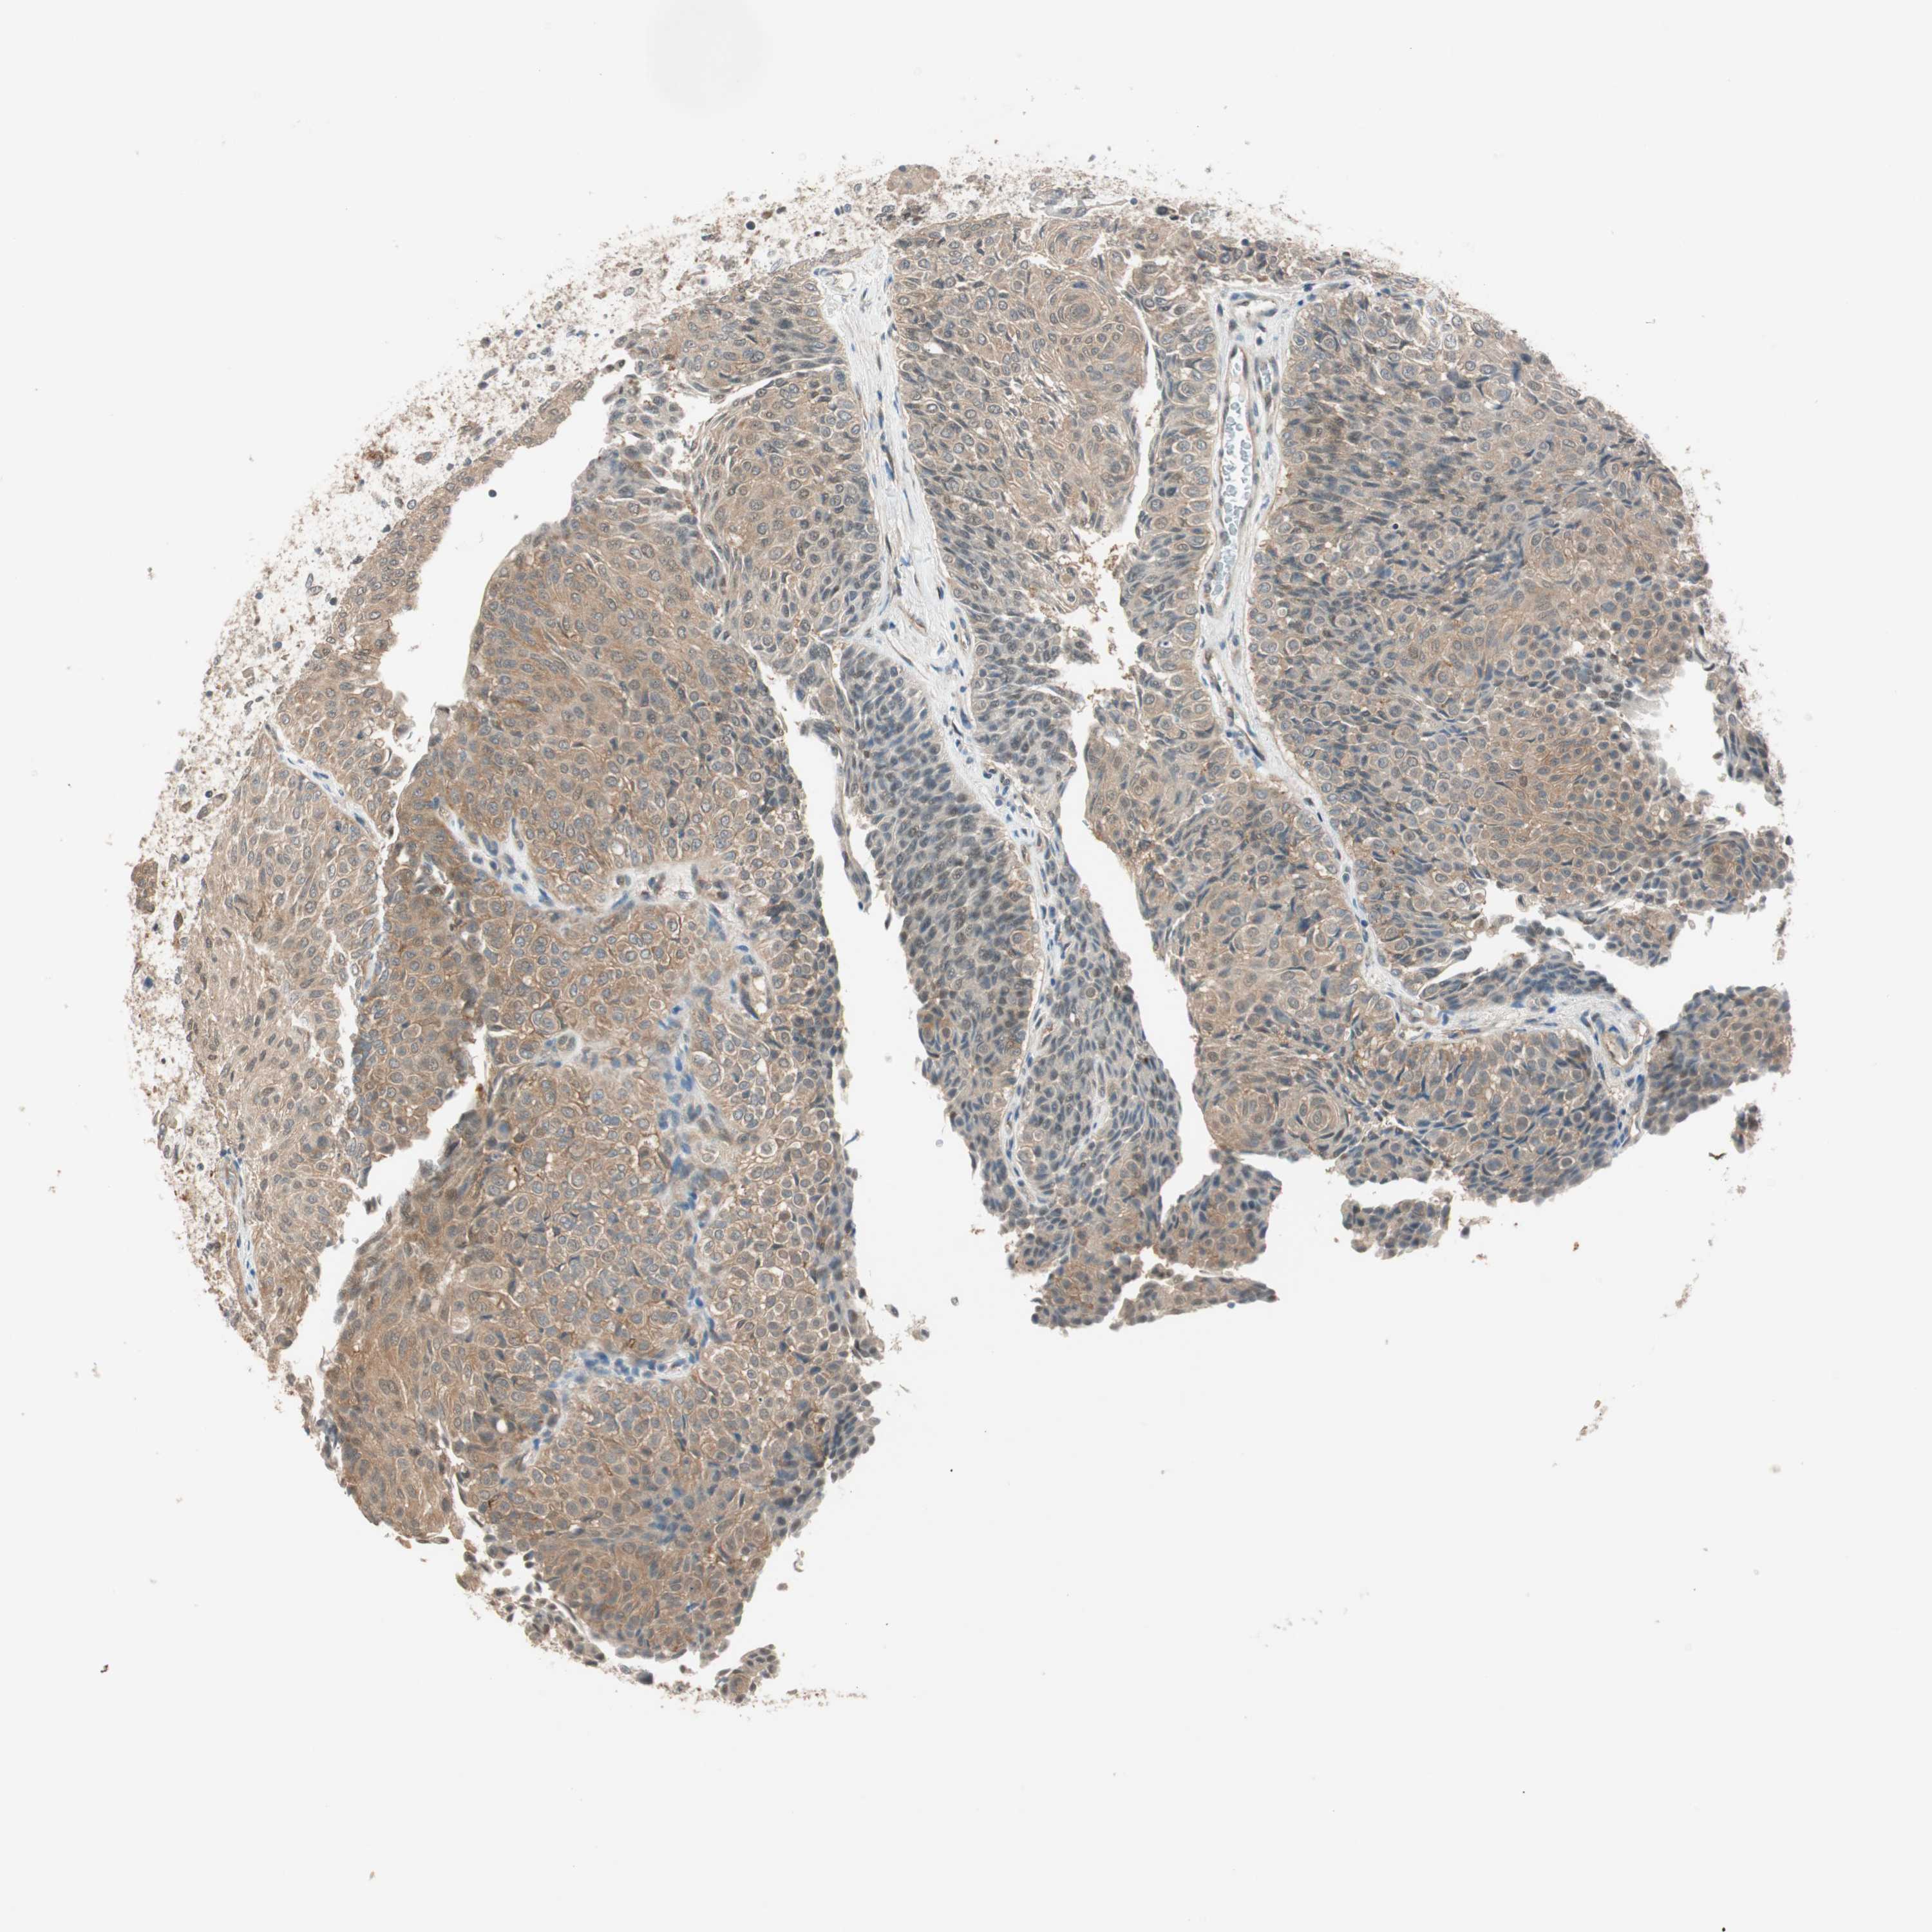

UROTHELIAL CANCER - Protein expressioni

A mouse-over function shows sample information and annotation data. Click on an image to view it in a full screen mode. Samples can be filtered based on level of antibody staining by selecting one or several of the following categories: high, medium, low and not detected. The assay and annotation is described here.

Note that samples used for immunohistochemistry by the Human Protein Atlas do not correspond to samples in the TCGA dataset.

Antibody stainingi

Antibody staining in the annotated cell types in the current human tissue is reported as not detected, low, medium, or high, based on conventional immunohistochemistry profiling in selected tissues. This score is based on the combination of the staining intensity and fraction of stained cells.

Each image is clickable and will lead to virtual microscopy that enables deeper exploration of all samples and also displays staining intensity scores, fraction scores and subcellular localization as well as patient and tissue information for each sample.

Antibody HPA006702

Antibody CAB021101

Urothelial carcinoma, Low grade

Urothelial carcinoma, High grade